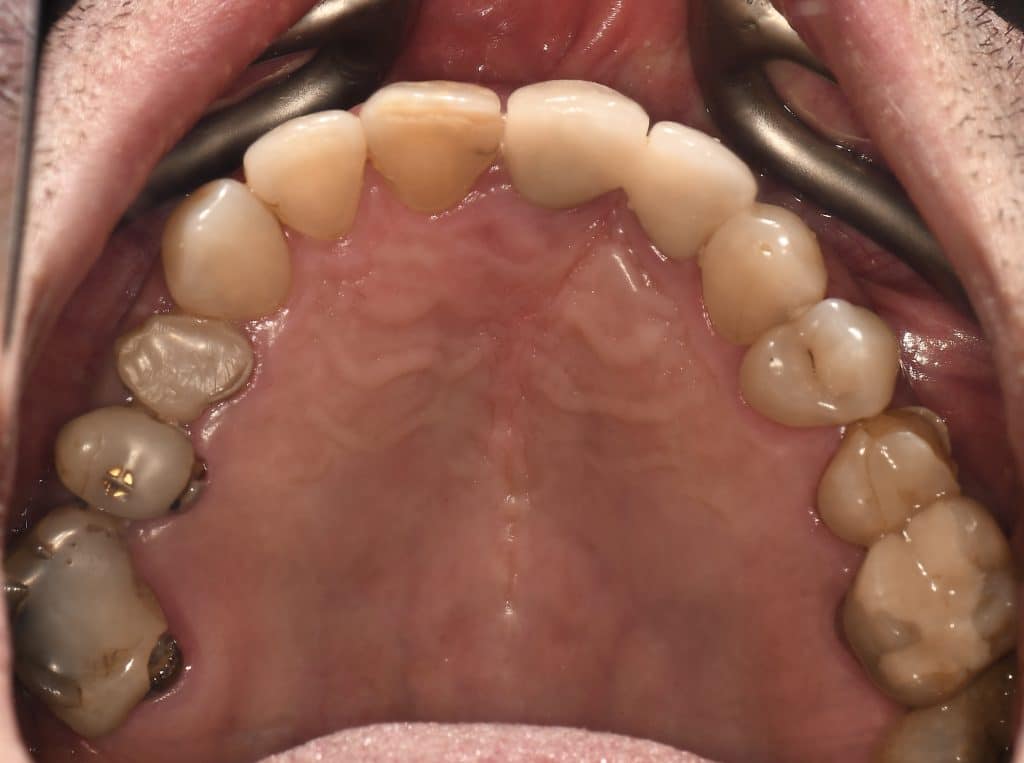

Case of the day where i extracted the 34-35-36 and an immediate placement of 2 implants in the 34-36 sites

sticky bone grafting GTO by osteobiol was used with straumann xenograft